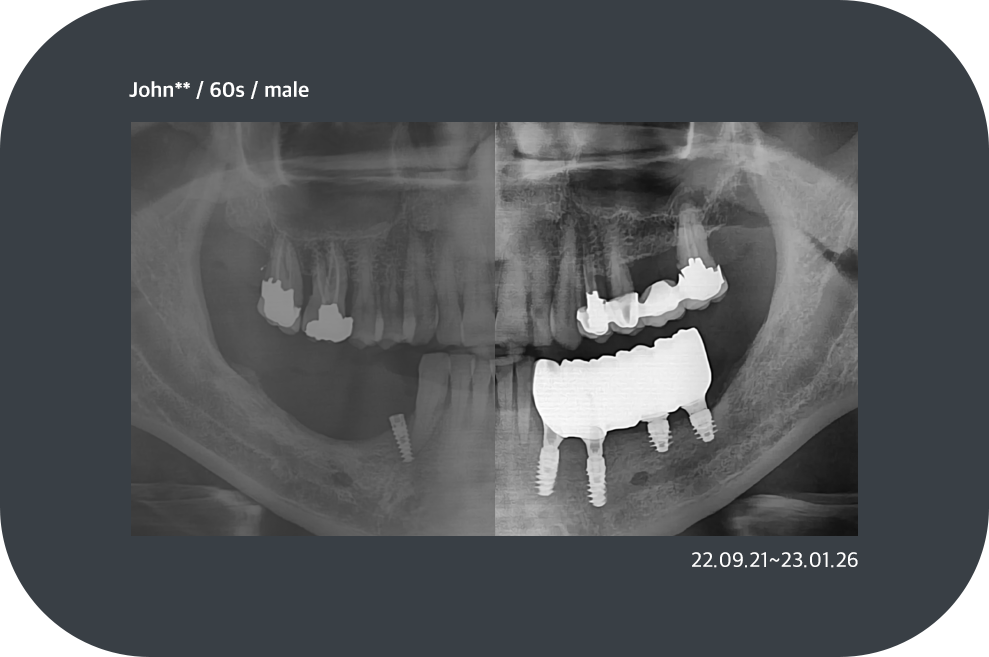

치료사례

임플란트 치료사례

*모든 증례 사진은 의료법 제23조, 제56조에 의거하여, 당사자의 동의하에 게시하였습니다.

*치료 사진은 모두 본원에서 치료한 환자분의 사진입니다.

*치료 사진은 모두 동일인의 사진이며, 동일조건에서 촬영하였습니다.

*개인의 차이에 따라 시술 및 수술 후 부작용이 발생할 수 있으며, 의료진과 충분한 상담을 받으시기 바랍니다.